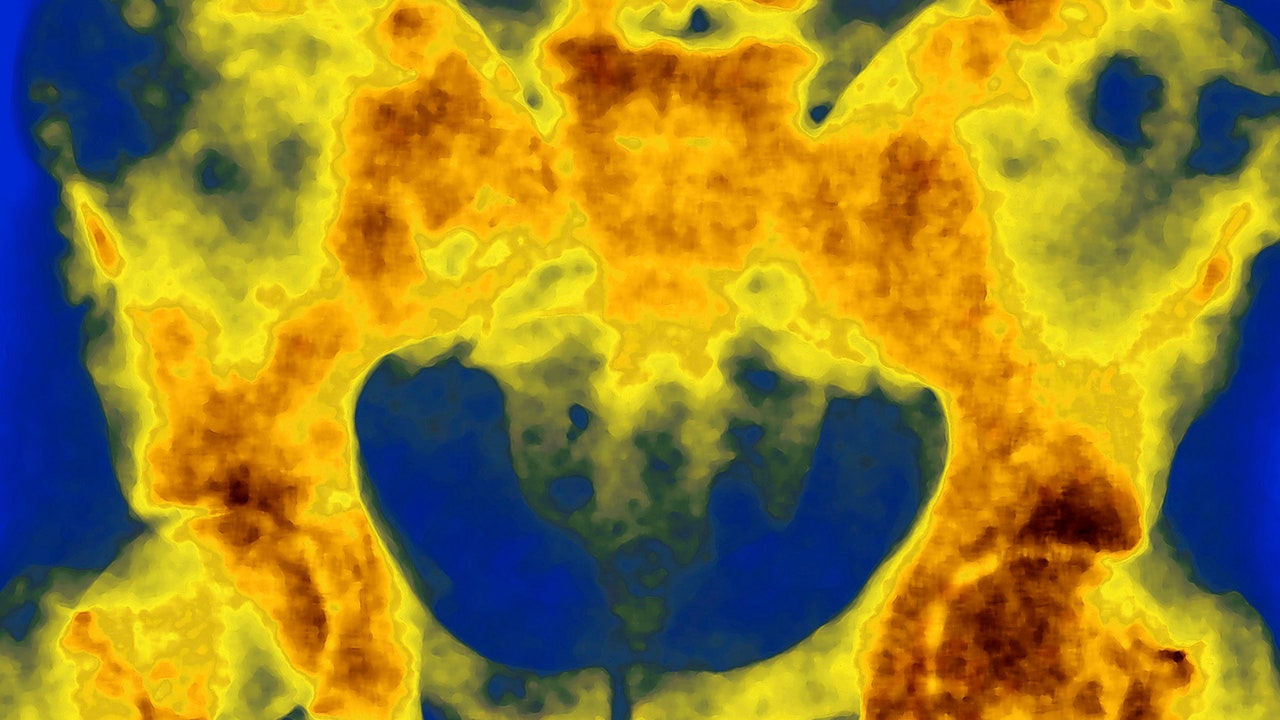

The study tested an emerging class of medicine called radiopharmaceuticals, drugs that deliver radiation directly to cancer cells. The drug in this case is a molecule that contains two parts: a tracker and a cancer-killing payload.

Trillions of these molecules hunt down cancer cells, latching onto protein receptors on the cell membrane. The payload emits radiation, which hits the tumor cells within its range.

When cancer is confined to the prostate, radiation can be beamed onto the body or implanted in pellets.

But those methods don’t work well in more advanced prostate cancer. About 43,000 men in the United States each year are diagnosed with prostate cancer that has spread and is no longer responding to hormone-blocking treatment.

The study tested a new way to get radiation treatment to such patients.